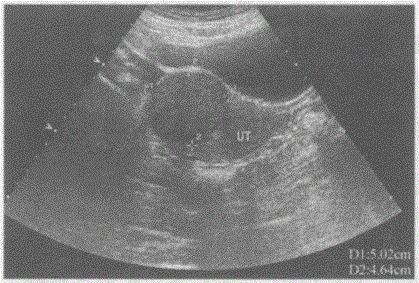

问题 临床资料:女,40岁,常规体检。 超声综合描述:子宫前位,宫底右前壁可见5.0cm×4.6cm稍低回声区,边界清晰,形态规则,内回声尚均匀,向包膜外突起,CDFI:稍低回声区内及周边可见丰富动静脉血流信号。见下图及彩图。 {图1} 超声提示:

选项 A.阔韧带肌瘤 B.子宫肌瘤(肌壁间) C.子宫肌瘤(黏膜下) D.子宫肌瘤(浆膜下)

答案 D